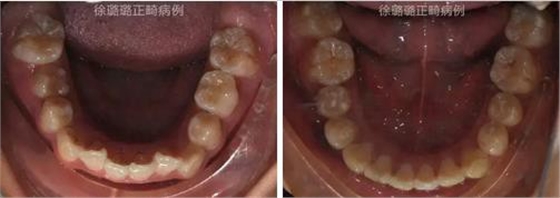

360截圖20170120124717490.jpg

口內(nèi)特征:恒牙早期,雙側(cè)磨牙關(guān)系為輕度遠(yuǎn)中關(guān)系,前牙深覆牙合 Ⅱ°,深覆蓋 6mm,上下頜牙弓中線不端正,上頜中線右偏 3mm,上頜前牙唇傾,下頜牙列輕度擁擠,右側(cè)上頜間隙不足,左側(cè)乳尖牙滯留,上頜左側(cè)乳尖牙對刃牙合,上下頜牙弓形態(tài)不對稱。